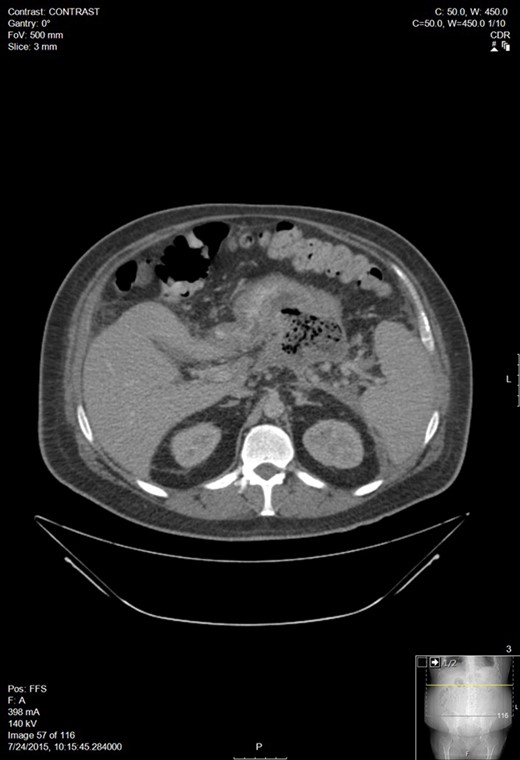

A week later, he presented to his PCP for follow up and was febrile with increasing abdominal pain. CT of the abdomen and pelvis showed an 11 Ă— 15 cm2 pancreatic fluid collection. His hemoglobin was 6.9 and he was transfused 3 units of PRBC. After transfer to our facility, a repeat CT showed a small pericardial and left pleural effusions, large volume ascites, a pancreatic fluid collection within the lesser sac between the anterior pancreas and posterior gastric body measuring 14 Ă— 16.1 Ă— 16.2 cm3, and blood in both paracolic gutters and pararenal spaces (Fig. 2). He was referred to Interventional Radiology for drain placement. After drainage, he clinically improved and was discharged.

Worsening walled off pancreatic necrosis with extension to the paracolic gutters.